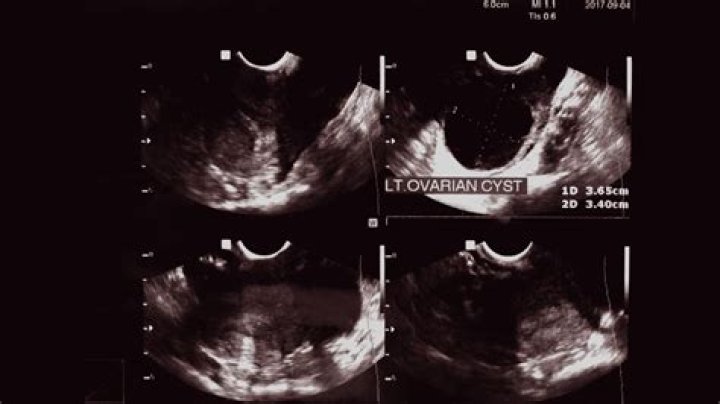

How do you detect ovarian cysts?

2. Ultrasound. An ultrasound can pinpoint the location, size, and makeup of ovarian cysts. ...